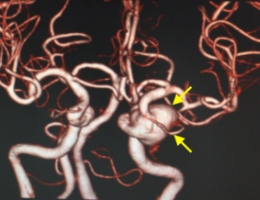

治療前

物が二重に見えるようになって発症した内頚動脈大型動脈瘤(矢印)の症例です。クリッピング術で直接動脈瘤をつぶすことができないため、バイパス術(矢印)を増設し内頚動脈を遮断することで動脈瘤を治療しました。